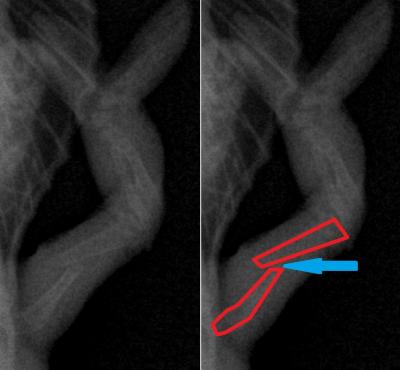

Majitelka si všimla zlomeniny této nožičky. Bílé čáry znázorňují přelomenou kost. Měly by na sebe navazovat a tvoři jednu linii.

Detailní záběr na frakturu stehenní kosti a dislokované fragmenty (rozlomená kost je znázorněna červeně).

Rozhodli jsme se jí řešit pomocí medulárního hřebu (jedná se o metodu, kdy se oba úlomky srovnají do původní polohy a středem kosti skrz dřeňovou dutinu se vede hřeb, který oba fragmenty pevně zafixuje ve fyziologické poloze).

Zavádění hřebu do dřeňové dutiny fragmentu kosti, který přidržujeme mikropinzetou. Na snímku vpravo je vše barevně schématicky zobrazeno.